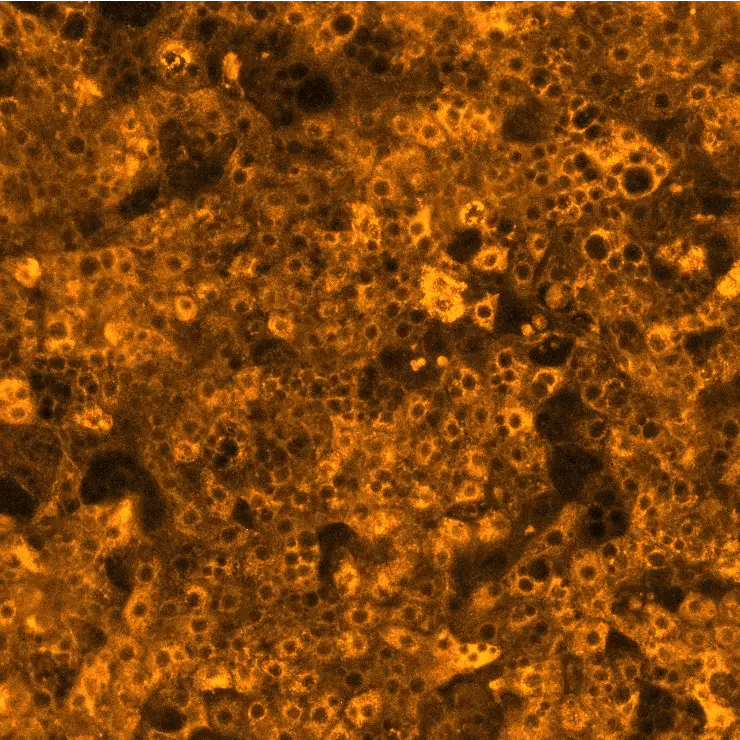

ioHepatocytes are human iPSC-derived hepatocytes, deterministically programmed using opti-ox technology. The cells display a cobblestone morphology, prominent nuclei and expression of core hepatocyte markers from day 4. The cells express phase I-III drug metabolism genes and maintain functional CYP3A, CYP2B6, and CYP1A2 enzymes to support advanced metabolic investigations. ioHepatocytes (Toxicology) also demonstrate DILI responses comparable to primary human hepatocytes, providing a highly predictive platform for hepatotoxicity assessment.